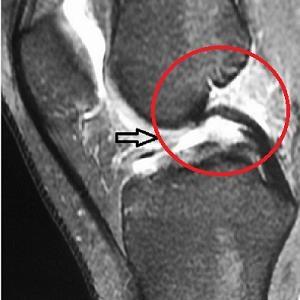

به حالتی از افزایش ترشح مایع مفصلی مفاصل سینوویال اطلاق می شود که از حالت طبیعی خود خارج شده است که میتواند ناشی از علائم التهابی عفونت آسیب های حاد سبب ترشح اگزودا و ترانسودا و یا حتی خون و بافت چربی باشد. مواردی از افیوژن مفصلی که شامل چربی و خون باشد را به نام لیپو همارتروز می نامند که در آسیب های حاد بیشتر دیده می شود.

این نوع آسیب بیشتر در آسیب رباط صلیبی خلفی دیده می شود و همچنین در خونریزی های استخوانی در انترومدیال کندیل فمور ۵۰% و انترومدیال کندیل تیبیا ۲۸% همچنین در آسیب عضله پوپلیتئوس ۳۳% ، در آسیب رباط داخلی بسیار شایع است.